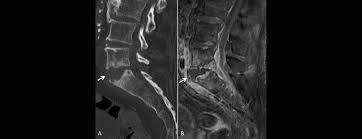

Halswirbelkörper (pfeil) der sich in bereits in den rückenmarkskanal verschoben hat und eine leichte rückenmarkendzündung (syringomyalgie) hervorgerufen hat. Die mrt ist die untersuchungsmethode der ersten wahl zur abklärung einer erkrankung an der halswirbelsäule. Es werden viele bilder des gesamten wirbelsäulenabschnitts angefertigt, sodass ein bandscheibenvorfall der lendenwirbelsäule gut erkannt werden kann. Verdacht auf bursitis hat sich nicht bestätigt, das mrt hüften waren o.b. Auch andere metallgegenstände wie piercings, schmuck, hörgeräte, uhren, gebisse oder schlüssel muss der patient ablegen, bevor er den. Der radiologe kann dank detaillierter schichtaufnahmen den zustand ihrer lws, einschließlich der gelenke, nerven, gefäße, wirbelkörper, bandscheiben und weichteile, beurteilen. Der arzt nennt diese verschiedenen aufnahmetechniken wichtungen. Noch länger muss auf die ergebnisse der forschung warten. Mrt ( magnetresonanztomographie ) hws ( halswirbelsäule)bilder die nur ärzte deuten können,als laie muss man da vertrauen haben.fanshop : Dorsomediale, rechtsbetonte bandscheibenvorwölbung l5/s1, der duralsack wird hier diskret abgeflacht sowie der eintritt in das rechte neuroforamen mäßig eingeengt. Mrt bilder kniegelenk sind musik in den ohren. Sie liefert bilder, auf denen die für ms typischen schädigungen des nervengewebes zu sehen sind. Lws ist frei, die schmerzen beginnen auch erst unter dem gesäß.

Aber entzündungen oder tumoren des knochens können mit der mrt dargestellt werden: Die mrt ist die untersuchungsmethode der ersten wahl zur abklärung einer erkrankung an der halswirbelsäule. Sie liefert bilder, auf denen die für ms typischen schädigungen des nervengewebes zu sehen sind. Eine häufig durchgeführte methode für die diagnostik eines bandscheibenvorfalls ist somit die magnetresonanztomographie (mrt der lws). Für mich sehen die bilder nicht sehr dramatisch aus aber ich hab ja auch keine ahnung. Manchmal können derartige radiologisch nachweisbare veränderungen aber auch fehlen. Mrt der lws t2 (linkes bild) weiß kann man die entzündung der lendenwirbelsäule erkennen, da die bandscheibe durch die fehlstellung aufgebraucht wurde und nun knochen auf knochen reibt und eine entzündung des knochens entsteht. Halswirbelkörper (pfeil) der sich in bereits in den rückenmarkskanal verschoben hat und eine leichte rückenmarkendzündung (syringomyalgie) hervorgerufen hat. Mrt der halswirbelsäule in sagitaler projektion. Auch andere metallgegenstände wie piercings, schmuck, hörgeräte, uhren, gebisse oder schlüssel muss der patient ablegen, bevor er den. Mrt der lws t2 (linkes bild) weiß kann man die entzündung der lendenwirbelsäule erkennen, da die bandscheibe durch die fehlstellung aufgebraucht wurde und nun knochen auf knochen reibt und eine entzündung des knochens entsteht. Die entzündung greift hierbei sekundär auf die bandscheibe über. Allerdings haben sie eine venenverengung.